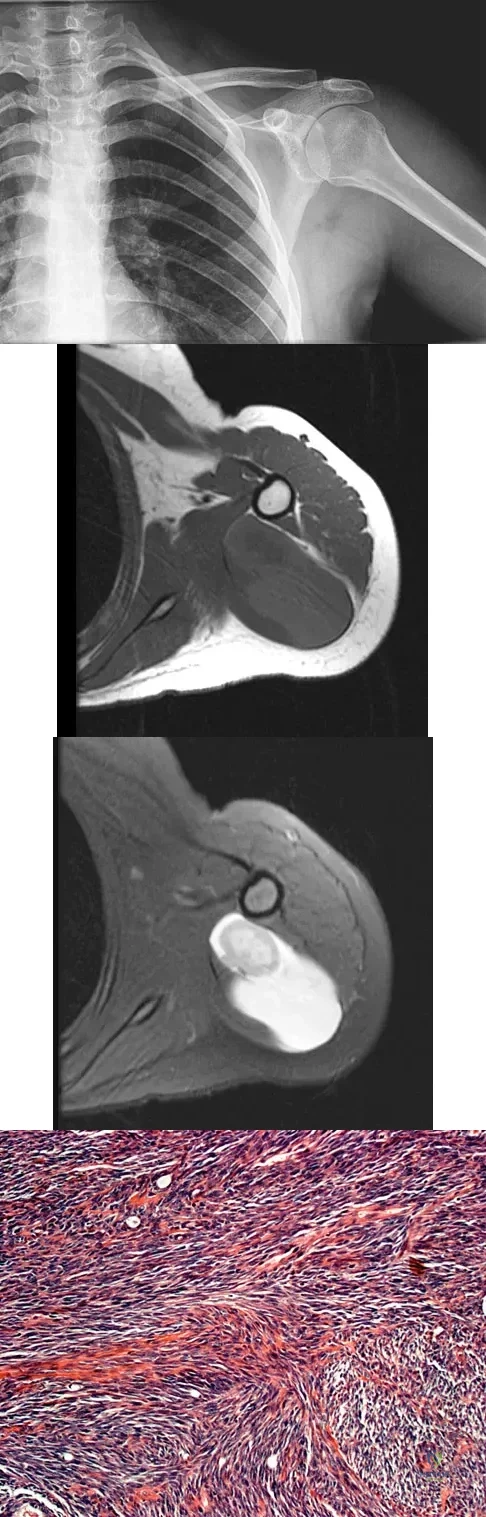

A 16-year-old girl has had painless swelling in her posterior left arm for the past 4 months. A radiograph, MRI scans, and an incisional biopsy specimen are shown in Figures 43a through 43d. What is the cytogenetic translocation most commonly associated with this tumor?

Explanation